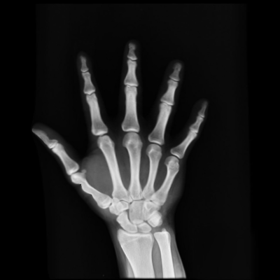

Figure 8. The second hand X-ray example.

We then consider another example of registering two hand X-ray images with larger deformations (see Fig. 8(a) for the source image, Fig. 8(b) for the target image, and Fig. 8(c) for their absolute intensity difference). The warped image produced by our proposed method (Fig. 8(d)) again closely resembles the target image with the intensity difference significantly reduced (see Fig. 8(e)). Fig. 8(f) shows that the mapping is smooth and bijective. For comparison, note that LDDMM [5] fails to match the fingers (Fig. 8(g)). While DROP [18] is capable of registering the fingers (Fig. 8(h)), it distorts the boundary shape of the overall image (Fig. 8(i)).